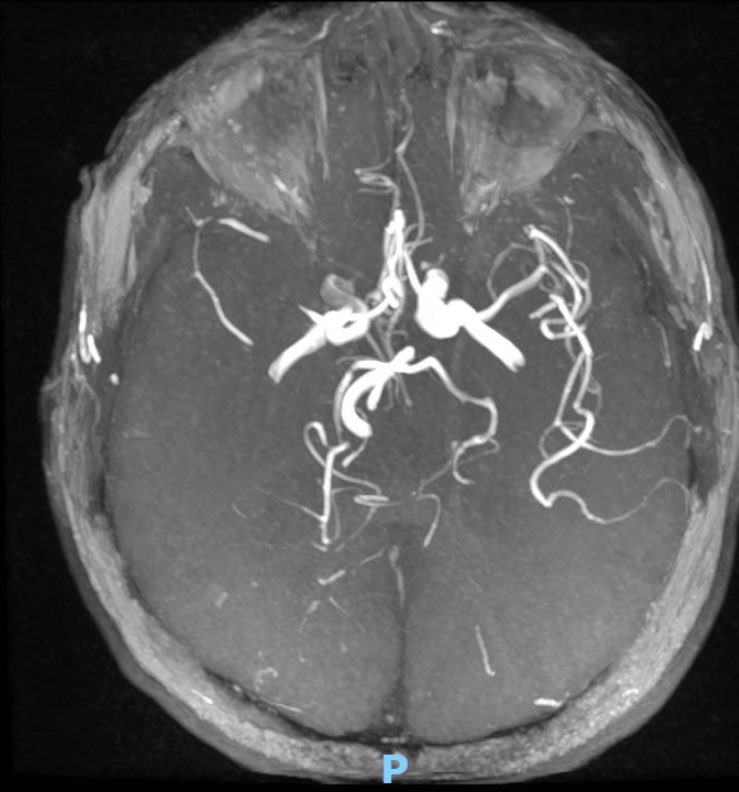

This 🧔♂️ presents with a subarachnoid haemorrhage in the left suprasellar cistern

DSA shows an infundibulum/ aneurysm of the left PCom. To coil or not was a conundrum. Every expert has a different take

Another asks for vessel wall imaging .

The size is 3.4 mm x 2.6 and it is located in the region of the bleed.